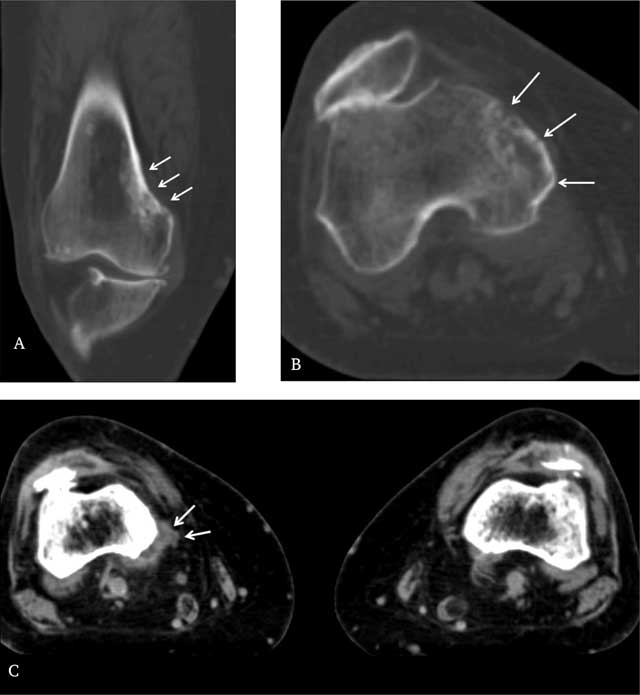

Figure 3

A. Coronal reconstructed CT image and B. axial CT image through distal right femur in bone window show the extent of the cortical metastases and underlying sclerosis more clearly (arrows). C. Axial CT scan through distal femur in soft tissue window shows a discrete associated soft tissue mass posteromedially on the right side, compared with the normal left side (arrows).